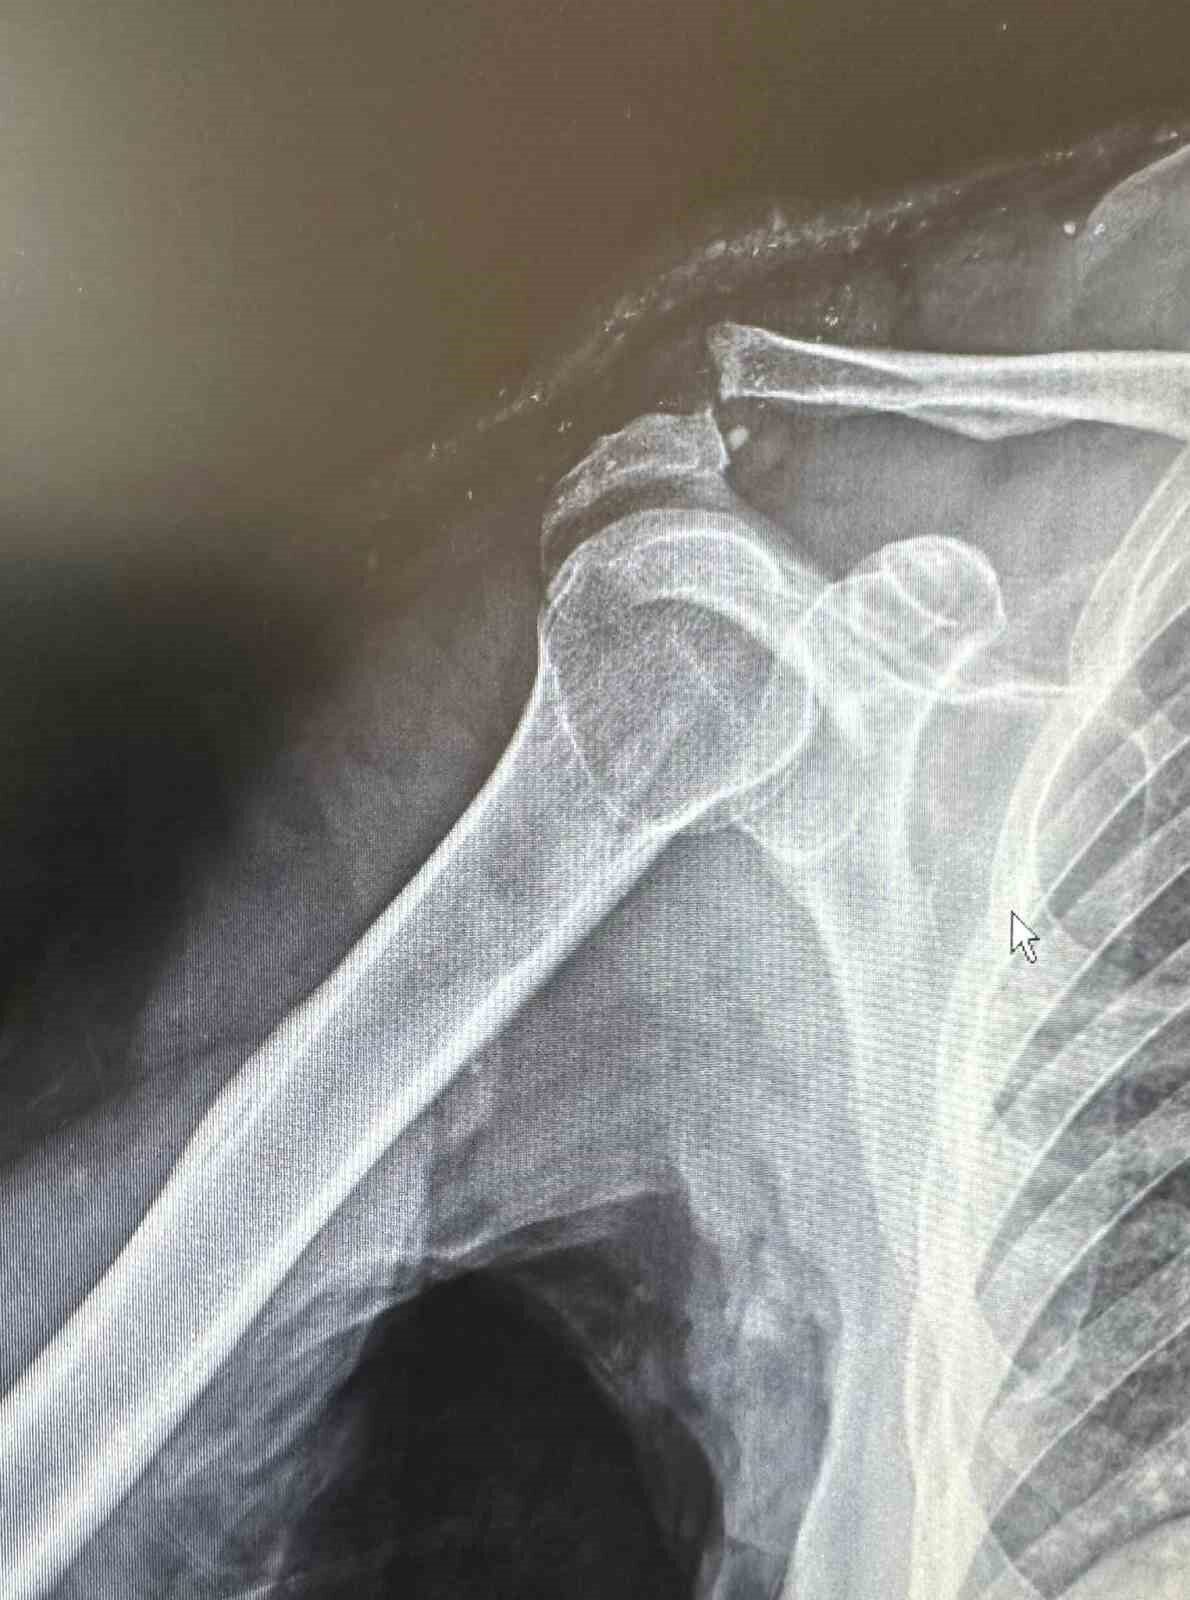

Olay, Mehmet Şerif Rençber’in tenis oynarken düştükten sonra omzunun çıkmasıyla meydana geldi. Rençber, tedavi için gittiği çeşitli sağlık kuruluşlarında yaşından dolayı ameliyat olamayacağını öğrendi. Ancak, Batman Eğitim ve Araştırma Hastanesi Ortopedi ve Travmatoloji Uzmanı Dr. Mehmet Yavuz Başer, özel bir plak kullanarak başarılı bir müdahale gerçekleştirdi.

Dr. Başer, durumuyla ilgili bilgi vererek, “Hastamız omuz çıkığı nedeniyle başvurdu. Çünkü tenis oynarken düşmesi sonucunda omzunda bir problemler oluştu. Genellikle bu tür yaralanmaları genç hastalarda görüyoruz. Ancak hastamız oldukça aktiftir. İlk değerlendirmede omuz eklemi yerinde değildi. Nadir kullanılan, hastanın kemik yapısına tam uyum sağlayan bir plak ile ameliyatı gerçekleştirdik,” ifadelerini kullandı.

Ameliyat sonrasında hastanın hızla fizik tedavi sürecine başlandığını belirten Dr. Başer, “Hastamız omuz hareketlerini yavaş yavaş yapmaya başladı. Yakında kol askısından kurtulacak ve 2-3 hafta içerisinde eski performansına dönecek,” diye ekledi.